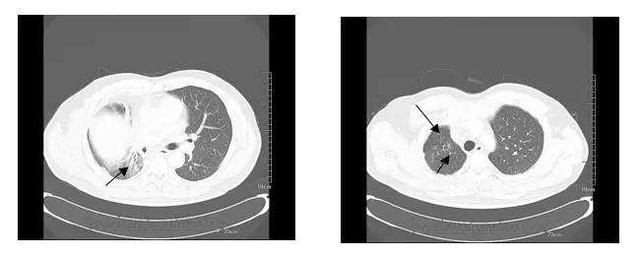

于是,2005年我在日本开始接受免疫细胞疗法。当进行到第2个疗程(第12次)时,终于,肿瘤有了缩小的趋势,腋下淋巴结的肿胀也逐渐消失了。在第2个疗程的第5次治疗时,右侧乳房中的其中1处的肿瘤奇迹般的完全消失了。剩下的1处肿瘤也缩小至1cm以下。

当第二个疗程结束时,经检测,我体内的肿瘤标志物也回到了正常值,右侧乳房的疼痛与肿胀感不适感也几乎消失了。当免疫细胞疗法告一段落后,我仍然积极配合日本诊所做随访工作,继续接受长期的观察,身体状况还算不错,整个人也变得精神了不少。